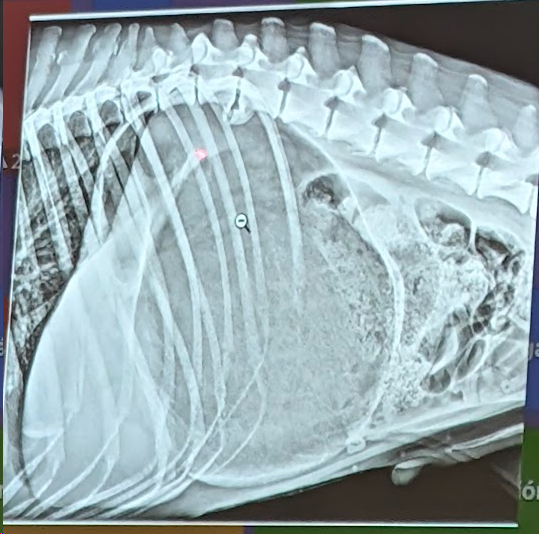

Preguna 7 - Multiple respuesta

- Hay efusion pleural

- Hay Hipertensión pulmonar (dilatación y tortuosidad de las arterias pulmonares, una prominencia del tronco pulmonar y un aumento del tamaño de las cavidades derechas del corazón. En este caso se ve porque si lo comparamos con la 9a costilla vemos que es mucho mas gruesa la arteria de la derecha que la costilla)